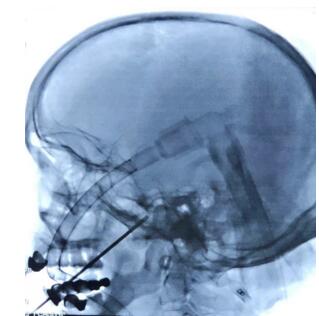

文世宏主任手术中

在征得患者及家属同意,做好充分的术前准备后,文世宏主任成功为患者施行了手术。该术式虽操作简单,但最大的难点便在于“穿刺”这一环了,这近乎于“盲穿”,对术者的操作技能要求极高!然而凭借敏锐的观察力与准确的判断力,文世宏主任轻轻松松就完成了这一操作,被同事笑称为“文一针”!

在C形臂引导下经嘴角外侧穿刺进入卵圆孔,将球囊导管送至半月神经节,充盈球囊,压迫数分钟,破坏神经传导,达到治疗目的。